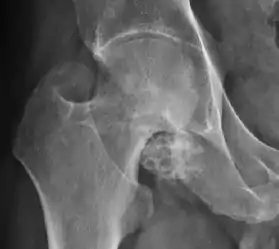

Synovial chondromatosis can be confidently diagnosed by X-ray when calcified cartilaginous chondromas are seen. However, other synovial proliferative processes, such as pigmented villonodular synovitis, require MRI for accurate diagnosis, although noncalcified synovitis can be suspected in radiographs by indirect signs, such as soft tissue swelling and/or erosions in the femoral head, femoral neck, or acetabulum (Figure 7).[1]

Figure 7:

Axial CT image of pigmented villonodular synovitis eroding the posterior cortex of the femoral neck.[1]

Sagittal T2* gradient echo image showing a posterior soft tissue mass with hypointense areas secondary to hemosiderin deposition.[1]

X-ray of synovial chondromatosis.[1]

CT of synovial chondromatosis.[1]

In synovial proliferative disorders, MRI demonstrates synovial hypertrophy. In the case of PVNS, characteristic foci of low signal intensity related to hemosiderin deposition are better seen on gradient echo T2* images (Figure 7). In the case of synovial osteochondromatosis, the synovial hypertrophy is accompanied by intermediate signal cartilaginous loose bodies and/or low signal calcified loose bodies.[1]